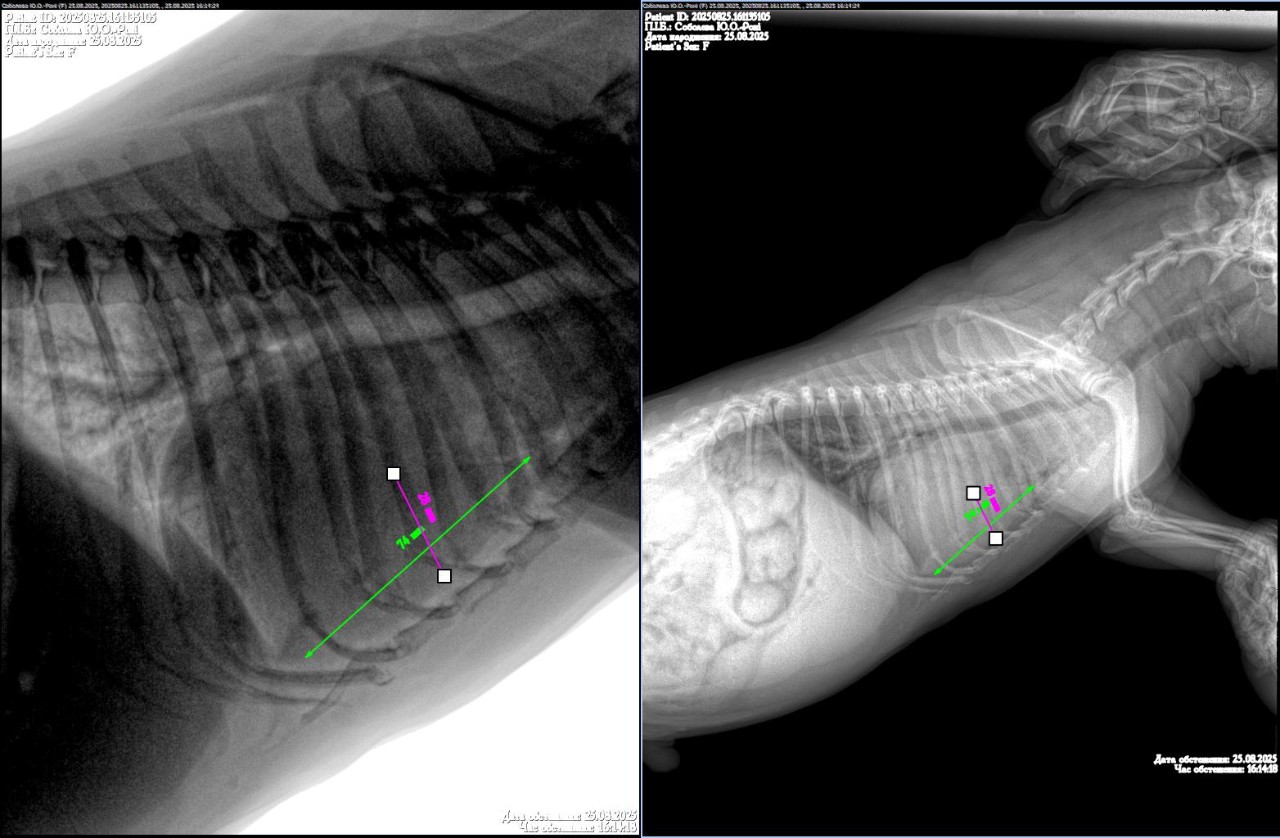

Добрый день уа. Врачи у меня неординая просьба к вам, так как мы находимся прифронтовой зоне и сейчас нет возможности выехать мы не можем помочь своему четверолапому. У него кашель, сердце исключили, сказали искать проблему в легких, рентген нам получилось сделать, а вот описание ренгена нет, ветгруппы нам не помогли. Если это возможно, помогите нам пожалуйста! Очень просим помощи, спасибо.